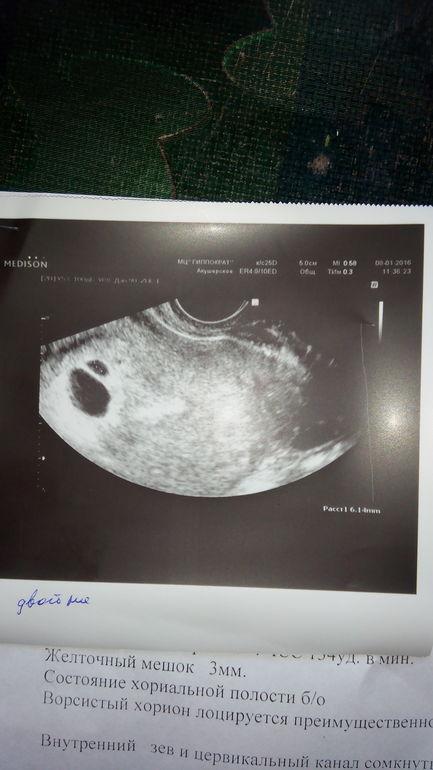

Подсаживали одного эмбриона, мажет с 8дпп, хгч растёт хорошо на 11 дпп 400 на 14 дпп 1200

Сегодня была на узи угрозы нет, но написали Двойня под вопросом!?

желаю здоровых двух деток, по теме не в курсе, но вижу 2 точечки и одна меньше другой, то что ассиметричная наверное не очень хорошо